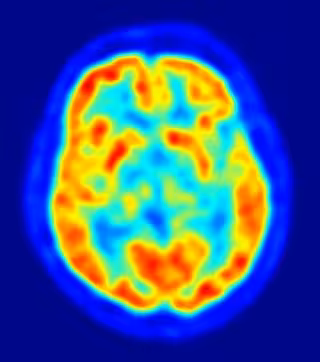

Un nuevo estudio ha desvelado una relación entre una proteína -que puede modificar el metabolismo celular en el cerebro- y la susceptibilidad a las convulsiones. La investigación, publicada en 'Neuron', podría conducir al desarrollo de nuevos tratamientos para la epilepsia.

La epilepsia es un trastorno caracterizado por convulsiones, y una actividad eléctrica anormal del cerebro. Algunos casos de epilepsia son resistentes a los tratamientos farmacológicos tradicionales, pero pueden mejorar mediante una dieta cetogénica -este tipo de dieta, que es muy baja en azúcares y alta en grasas, fuerza a las neuronas a cambiar su combustible habitual, la glucosa, por un tipo de subproducto de la grasa, llamado cuerpo cetónico.

Para examinar cómo la alteración del metabolismo puede proteger al cerebro de los ataques, Danial, y el coautor principal, Gary Yellen, estudiaron el papel de una proteína llamada BAD (BCL-2- agonista asociado de muerte celular), que modula el metabolismo de la glucosa en múltiples tipos de células.

Esto permitió realizar un análisis del metabolismo energético alterado, sin manipulaciones dietéticas drásticas -que pueden tener complejos y, en ocasiones, adversos efectos sistémicos. Los investigadores descubrieron que las modificaciones de BAD redujeron el metabolismo de la glucosa, y aumentaron el metabolismo de los cuerpos cetónicos en el cerebro, lo cual está asociado con una disminución de la susceptibilidad a las crisis epilépticas.

En conjunto, los hallazgos identifican BAD como un regulador del metabolismo energético del cerebro, e implican a esta proteína en la regulación de las convulsiones.